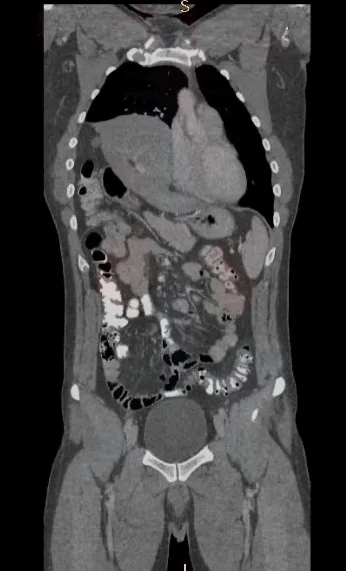

La presentación estuvo a cargo de los residentes de cirugía Belén Iriberry, Brayan Estrada y Yuri Andrade, mientras que la cirugía fue realizada por los médicos cirujanos Diego González y Elías Pérez.

Al hablar con Señal Calafate, el Dr. Gonzalez dio mas detalles de la cirugía que les valió el prestigioso reconocimiento.